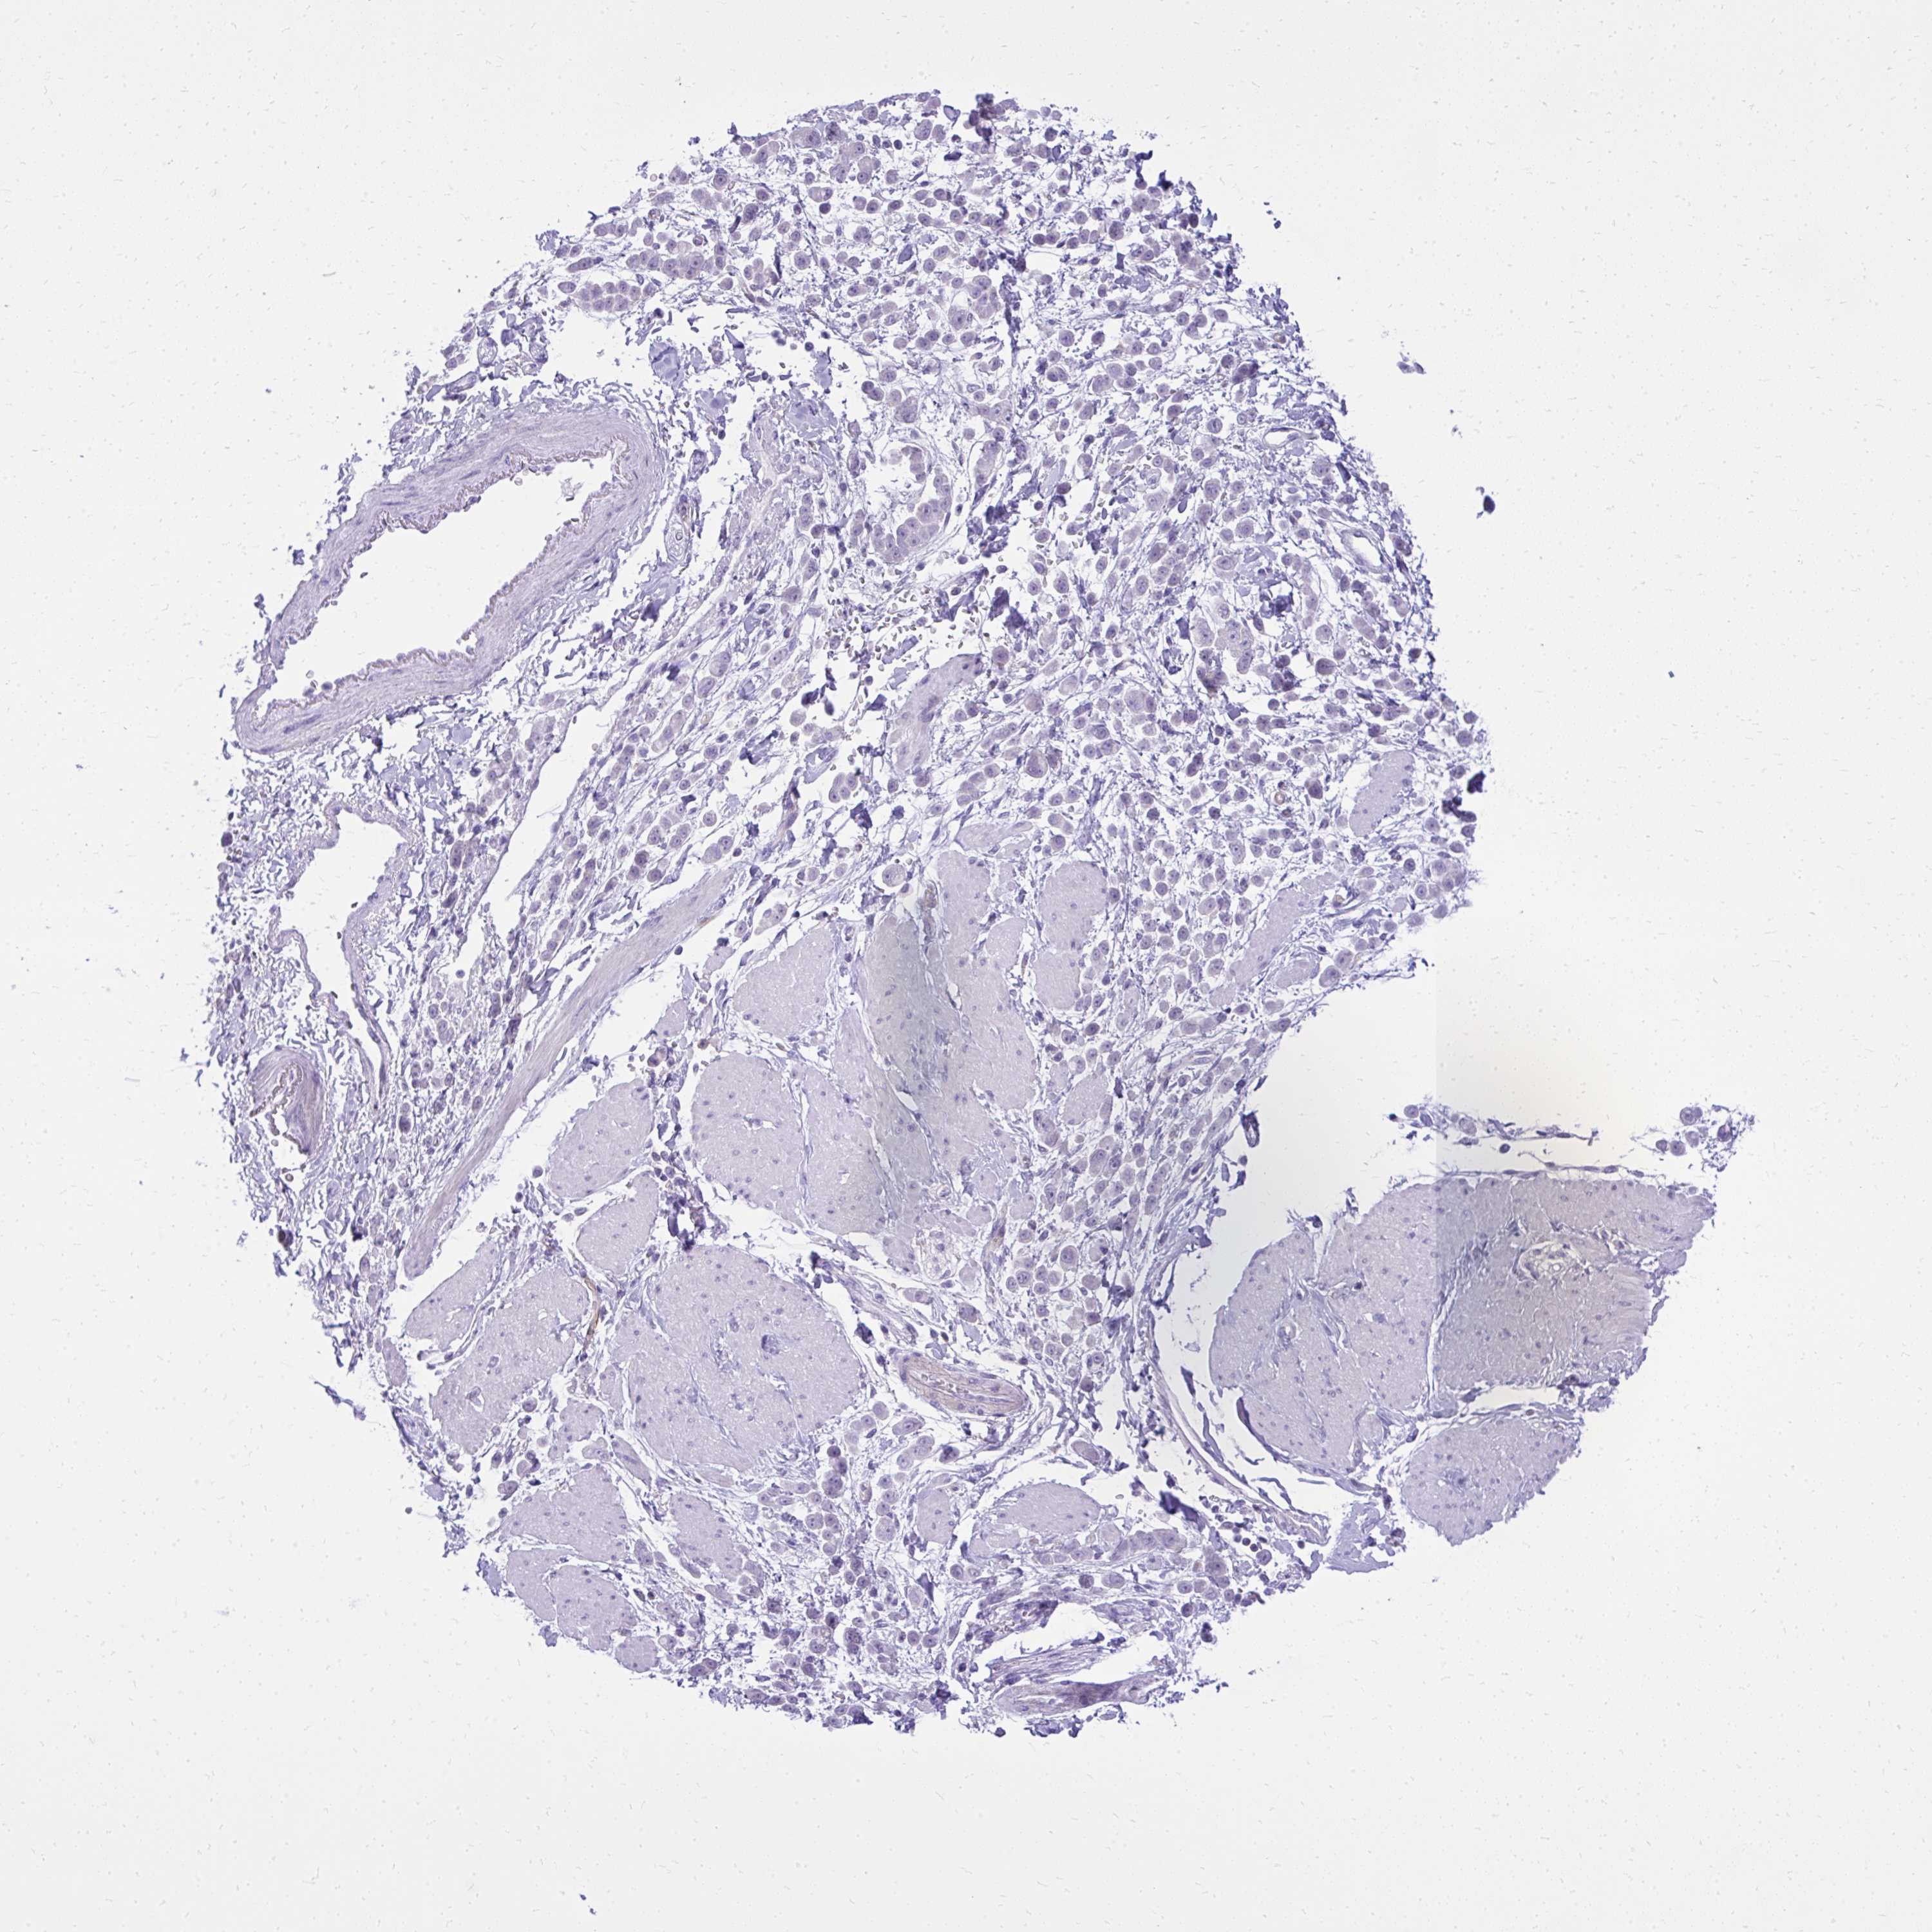

PANCREATIC CANCER - Protein expressioni

A mouse-over function shows sample information and annotation data. Click on an image to view it in a full screen mode. Samples can be filtered based on level of antibody staining by selecting one or several of the following categories: high, medium, low and not detected. The assay and annotation is described here.

Note that samples used for immunohistochemistry by the Human Protein Atlas do not correspond to samples in the TCGA dataset.

Antibody stainingi

Antibody staining in the annotated cell types in the current human tissue is reported as not detected, low, medium, or high, based on conventional immunohistochemistry profiling in selected tissues. This score is based on the combination of the staining intensity and fraction of stained cells.

Each image is clickable and will lead to virtual microscopy that enables deeper exploration of all samples and also displays staining intensity scores, fraction scores and subcellular localization as well as patient and tissue information for each sample.

Antibody HPA057666

Antibody HPA059092

Adenocarcinoma, NOS